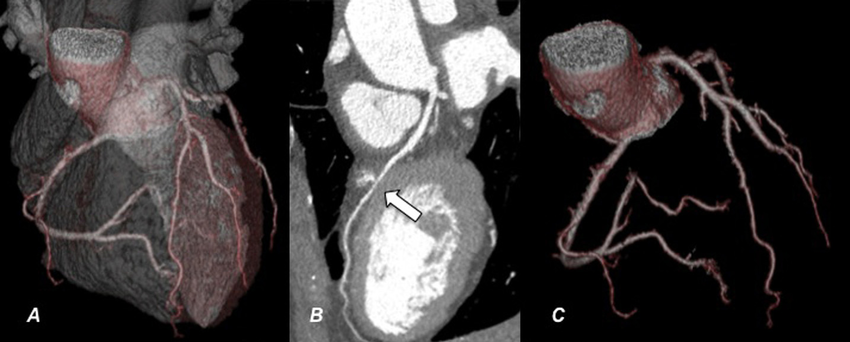

CT Coronarographie Privé Montréal – Advanced Cardiac Imaging

CT coronarographie privée in Montreal provides detailed visualization of the coronary arteries to assess heart health without invasive procedures. This advanced imaging exam helps detect plaque buildup, arterial narrowing, and early signs of coronary artery disease. The scan is fast, accurate, and interpreted by experienced radiologists.